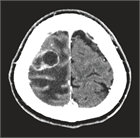

1. 単発・少数転移例では、3 cm以上の大きさの腫瘍に対しては、分割定位放射線照射も行われるが、放射線壊死のリスクも高くなるため、全身状態が安定している患者に対しては手術が第1選択で行われる(推奨度2)。2 cm以上で、症候性でmass effectがあれば手術適応としてもよい。